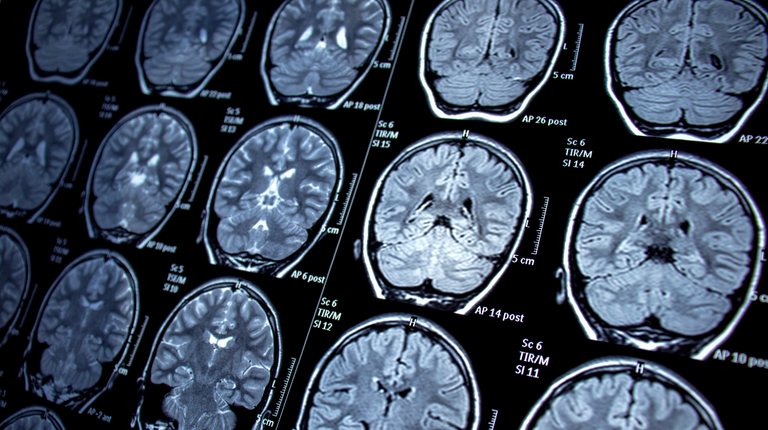

وبهذا الصدد، قال الدكتور ميليند سوفاني، استشاري طب الجهاز التنفسي (إخصائي أمراض الرئة) في مستشفيات جامعة نوتنجهام في المملكة المتحدة، لمجلة نيوزويك: "الوفاة أثناء نومك عادة ما تكون مرتبطة بالقلب أو الرئتين أو الدماغ، وفي بعض الأحيان، يمكن أن يموت مرضى السكري أثناء نومهم بسبب انخفاض مستويات الجلوكوز".

كما يمكن أن تشكل الأمراض العصبية مثل الصرع مخاطر أيضا، إذ إن الأشخاص المصابين بالصرع المقاوم للعلاج هم أكثر عرضة لمتلازمة تُعرف باسم الموت المفاجئ في الصرع Sudden Unexpected Death In Epilepsy (SUDEP)، والتي يُعتقد أنها ناجمة عن نوبات تؤثر على وظائف الجسم التنفسية والقلبية والكهربائية.

وبالمثل، فإن ارتفاع ضغط الدم الذي لا يمكن السيطرة عليه يمكن أن يزيد من خطر الإصابة بالسكتات الدماغية، والتي يمكن أن تكون قاتلة وتحدث أثناء النوم.